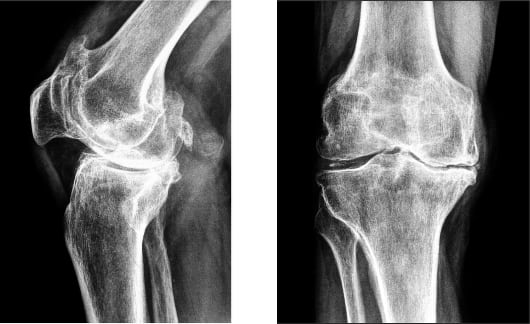

- остеопороз. Патология связана с низкой плотностью костной ткани вследствие ее неправильного формирования. Боль в коленном суставе при этом тупая и ноющая, убрать ее не так просто. Кости при этой патологии сильно подвержены переломам;

- ревматоидный артрит. Это системная патология, которая характеризуется воспалением соединительной ткани. Свое активное развитие она начинает при снижении защитных функций организма. Проявляется чувством скованности, которое человек может ощутить после длительного пребывания в состоянии покоя;